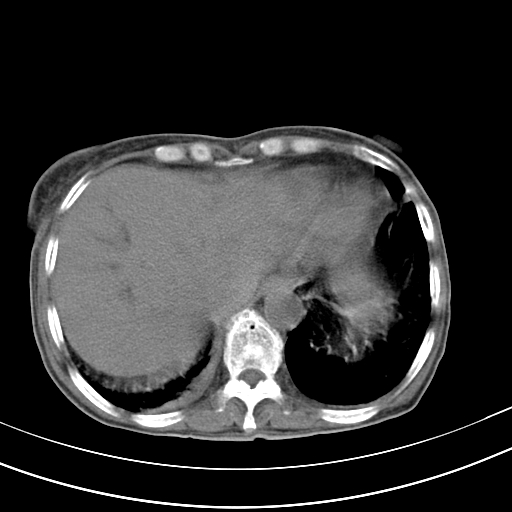

病人上腹部胀痛拌全身黄染八天

结石好象不明显吧?胆管稍扩张。

右侧少量胸水,胆囊增大,肝内胆管扩张,肝门部结构杂乱,建议增强。

考虑胰头癌或胰腺炎

肝内胆管及胰管扩张考虑为胰头区占位,肝门淋巴结增多,肝内多发低密度影,考虑为转移。门脉高压,脾大,胆囊大。

肝内胆管及胰管扩张,胰头增大考虑为胰头区占位,肝门淋巴结增多,考虑为转移。建议增强,脾大,胆囊大,壁厚,慢性胆囊炎。胃壁好像也增厚,且有一肿物。

胆囊增大,肝管扩张

脾大,

腹水,右胸腔少量积液。

胰腺炎。

1)考虑胰头癌并胆系低位梗阻;建议行ct增强扫描检查。2)慢性胆囊炎。3)脾大。4)少量腹水。5)双侧少量胸腔积液。